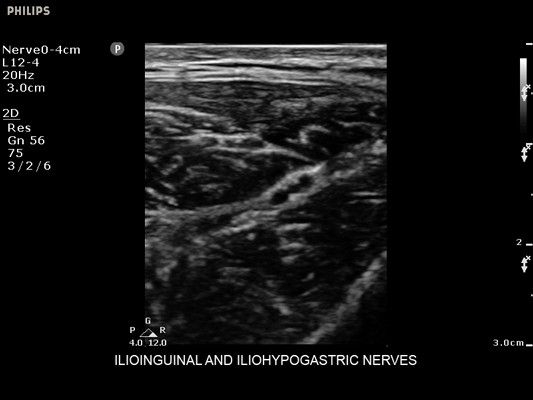

• Усиленная визуализация иглы без потери качества изображения окружающих тканей

• Метки центральной линии на датчиках L12-4 и C6-2 для упрощения внеплоскостной навигации

• Диагностика нервов

• Линейный УЗИ датчик Philips L12-4